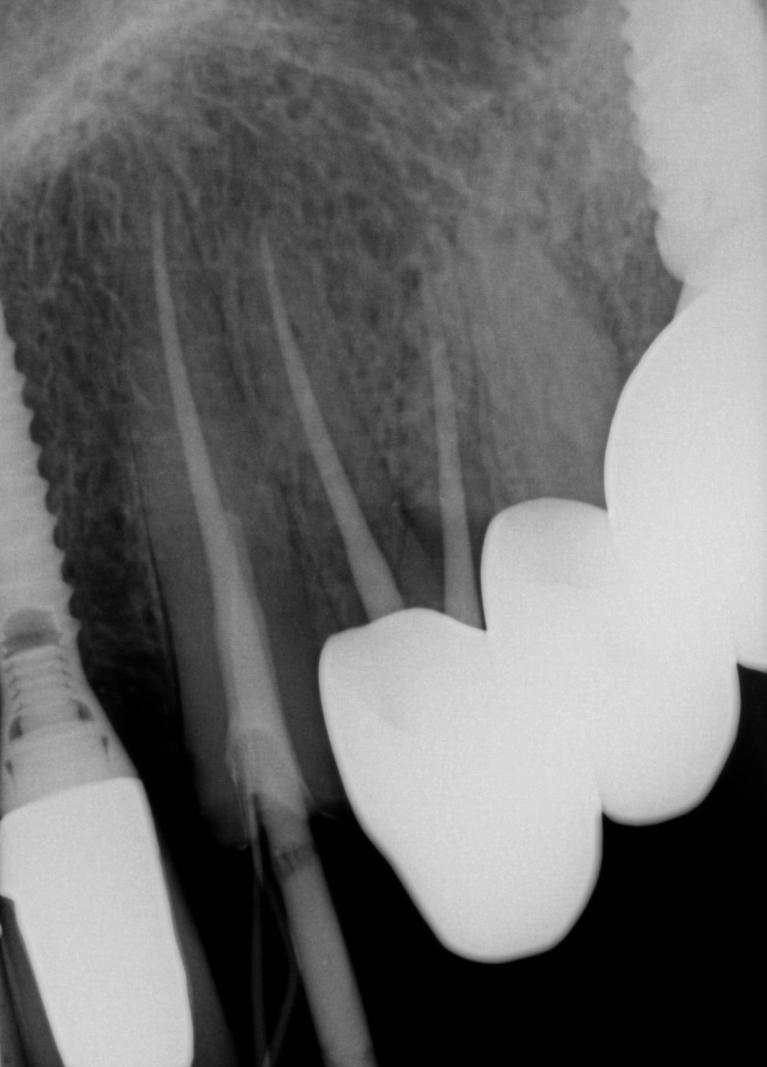

Does my broken tooth have to be pulled?

There is so many advertisements on the tv and radio that are talking about implants.  Implants are a great tool to replace a broken tooth,Tooth Broken At Gumline or teeth, that can not be restored.  With so much emphasis on implants lately, patients often forget that our main goal is to try to save your teeth, not just pull them for implants.  When you break a tooth, you come in and we will give it a thorough evaluation.  Assuming there is enough healthy tooth to work with, and there is no major periodontal (gum) problems to compromise things, we are likely to present you with options to save your broken tooth.  ...